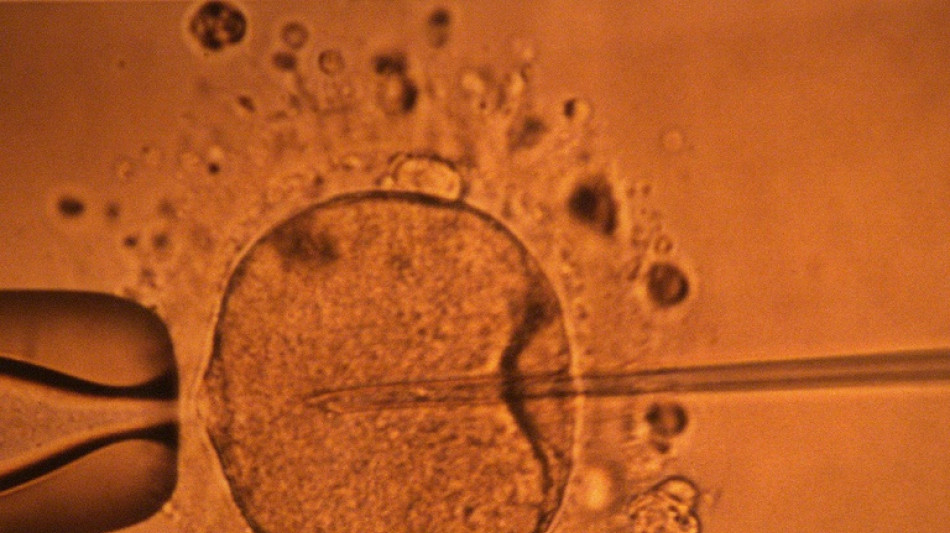

Un estudio apoya hipótesis de disminución mundial de concentración de espermatozoides

Un estudio apoya hipótesis de disminución mundial de concentración de espermatozoides / Foto: MARCEL MOCHET - AFP/Archivos

La concentración de espermatozoides, uno de los factores de la fertilidad masculina, disminuyó significativamente en todo el planeta en las últimas décadas, según un estudio publicado el martes.

"La concentración de espermatozoides disminuyó significativamente entre 1973 y 2018", resumen los autores de este trabajo publicado en la revista Human Reproduction Update y realizado mediante la compilación de unos 40 estudios previos.